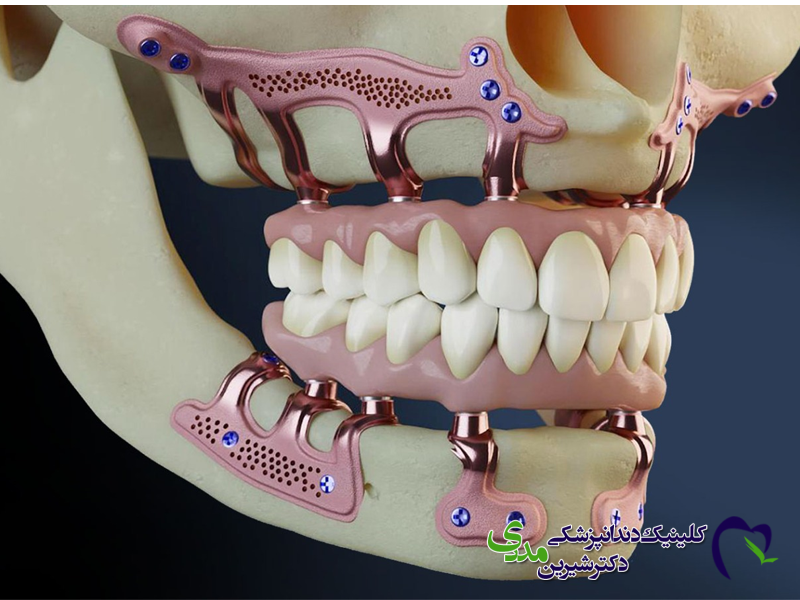

اوردنچر چیست؟

اوردنچر نوعی دندان مصنوعی متحرک است که روی چندین ایمپلنت دندان ثابت می شود. این روش معمولاً برای افرادی که تمام دندان های فک بالا یا پایین خود را از دست داده اند، مناسب است. اوردنچر روی ۲ تا ۴ ایمپلنت قرار می گیرد و بیمار می تواند آن را برای تمیز کردن خارج کند. این روش ترکیبی از مزایای دندان مصنوعی متحرک و پایداری ایمپلنت است.

اوردنچر: پروتزی متحرک است که یک پایه پلاستیکی به رنگ لثه دارد و روی آن دندان های مصنوعی قرار گرفته است. این پروتز روی ایمپلنت ها قفل می شود اما توسط خود بیمار قابل خارج کردن است.

اوردنچر: گزینه ای اقتصادی تر برای جایگزینی کل دندان های یک فک است. تنها با ۲ تا ۴ ایمپلنت می توان یک پروتز کامل فک را با موفقیت نگه داشت.

اوردنچر: اگرچه روی ایمپلنت های ثابت سوار می شود، اما خود پروتز متحرک است. بیمار می تواند آن را برای تمیز کردن خارج کند.

اوردنچر، دارای یک پایه پلاستیکی است که بخشی از لثه را نیز می پوشاند. اگرچه این پایه به رنگ لثه ساخته می شود، اما ممکن است برای برخی افراد، تفاوت جزئی با لثه طبیعی احساس شود.